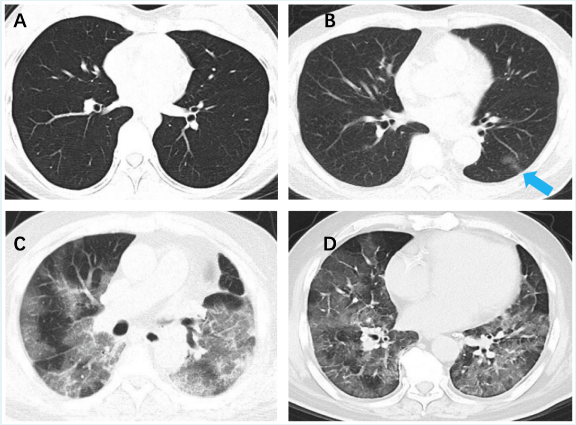

答:正常的肺组织充满大量的气体,气体在X线检查(包括:胸部平片和CT)图像中显示为黑色密度,因此正常的肺CT应该以黑色为主,其中可以看到一些像树枝一样的线条是肺血管和支气管等正常结构,如图A所示。当肺内出现炎症、水肿、出血等病变时,肺组织内会被炎症细胞、黏液、渗出液等物质填充,对X射线的透过度下降,肺CT就会出现一些白色的阴影。这些阴影可以仅累及很小的范围(就像图B中蓝色箭头所指部位),也可以像图C和图D这样影响到大面积的肺部组织。所以,肺部感染会导致肺内部分区域发白,但并不一定达到“白肺”的程度。